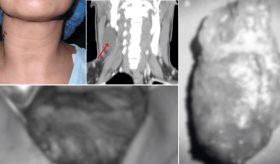

Para evaluar los efectos, se midieron las respuestas cerebrales mediante imágenes de resonancia magnética funcional, así como los niveles hormonales y las sensaciones subjetivas de hambre antes y después de la ingesta.

Los resultados, como señala el portal Intramed, mostraron que el consumo agudo de sucralosa, en comparación con la sacarosa, produjo un aumento del flujo sanguíneo en el hipotálamo (p<0,018), una mayor sensación de hambre (p<0,001) y ausencia de respuesta hormonal de saciedad. En términos generales, los hallazgos pueden interpretarse en las siguientes direcciones: